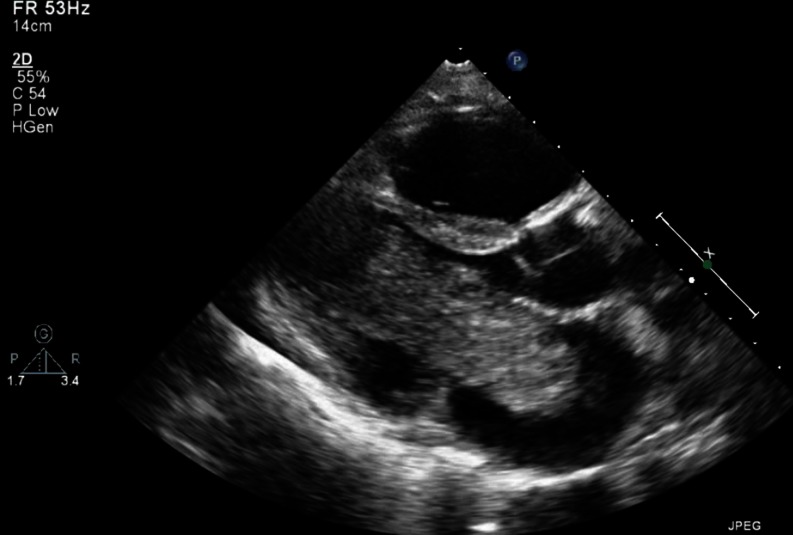

A transthoracic echocardiogram showed a large mass in the left atrium with obstruction of the mitral valve and pulmonary hypertension (Fig. 1). The diagnosis of cardiac myxoma was made and the patient was referred for resection of the mass. This proceeded without complications and pathological analysis confirmed the diagnosis of myxoma.

Fig. 1.

Transthoracic echocardiogram, parasternal long axis, showing a large mass in the left atrium protruding through the mitral valve into the left ventricle during diastole